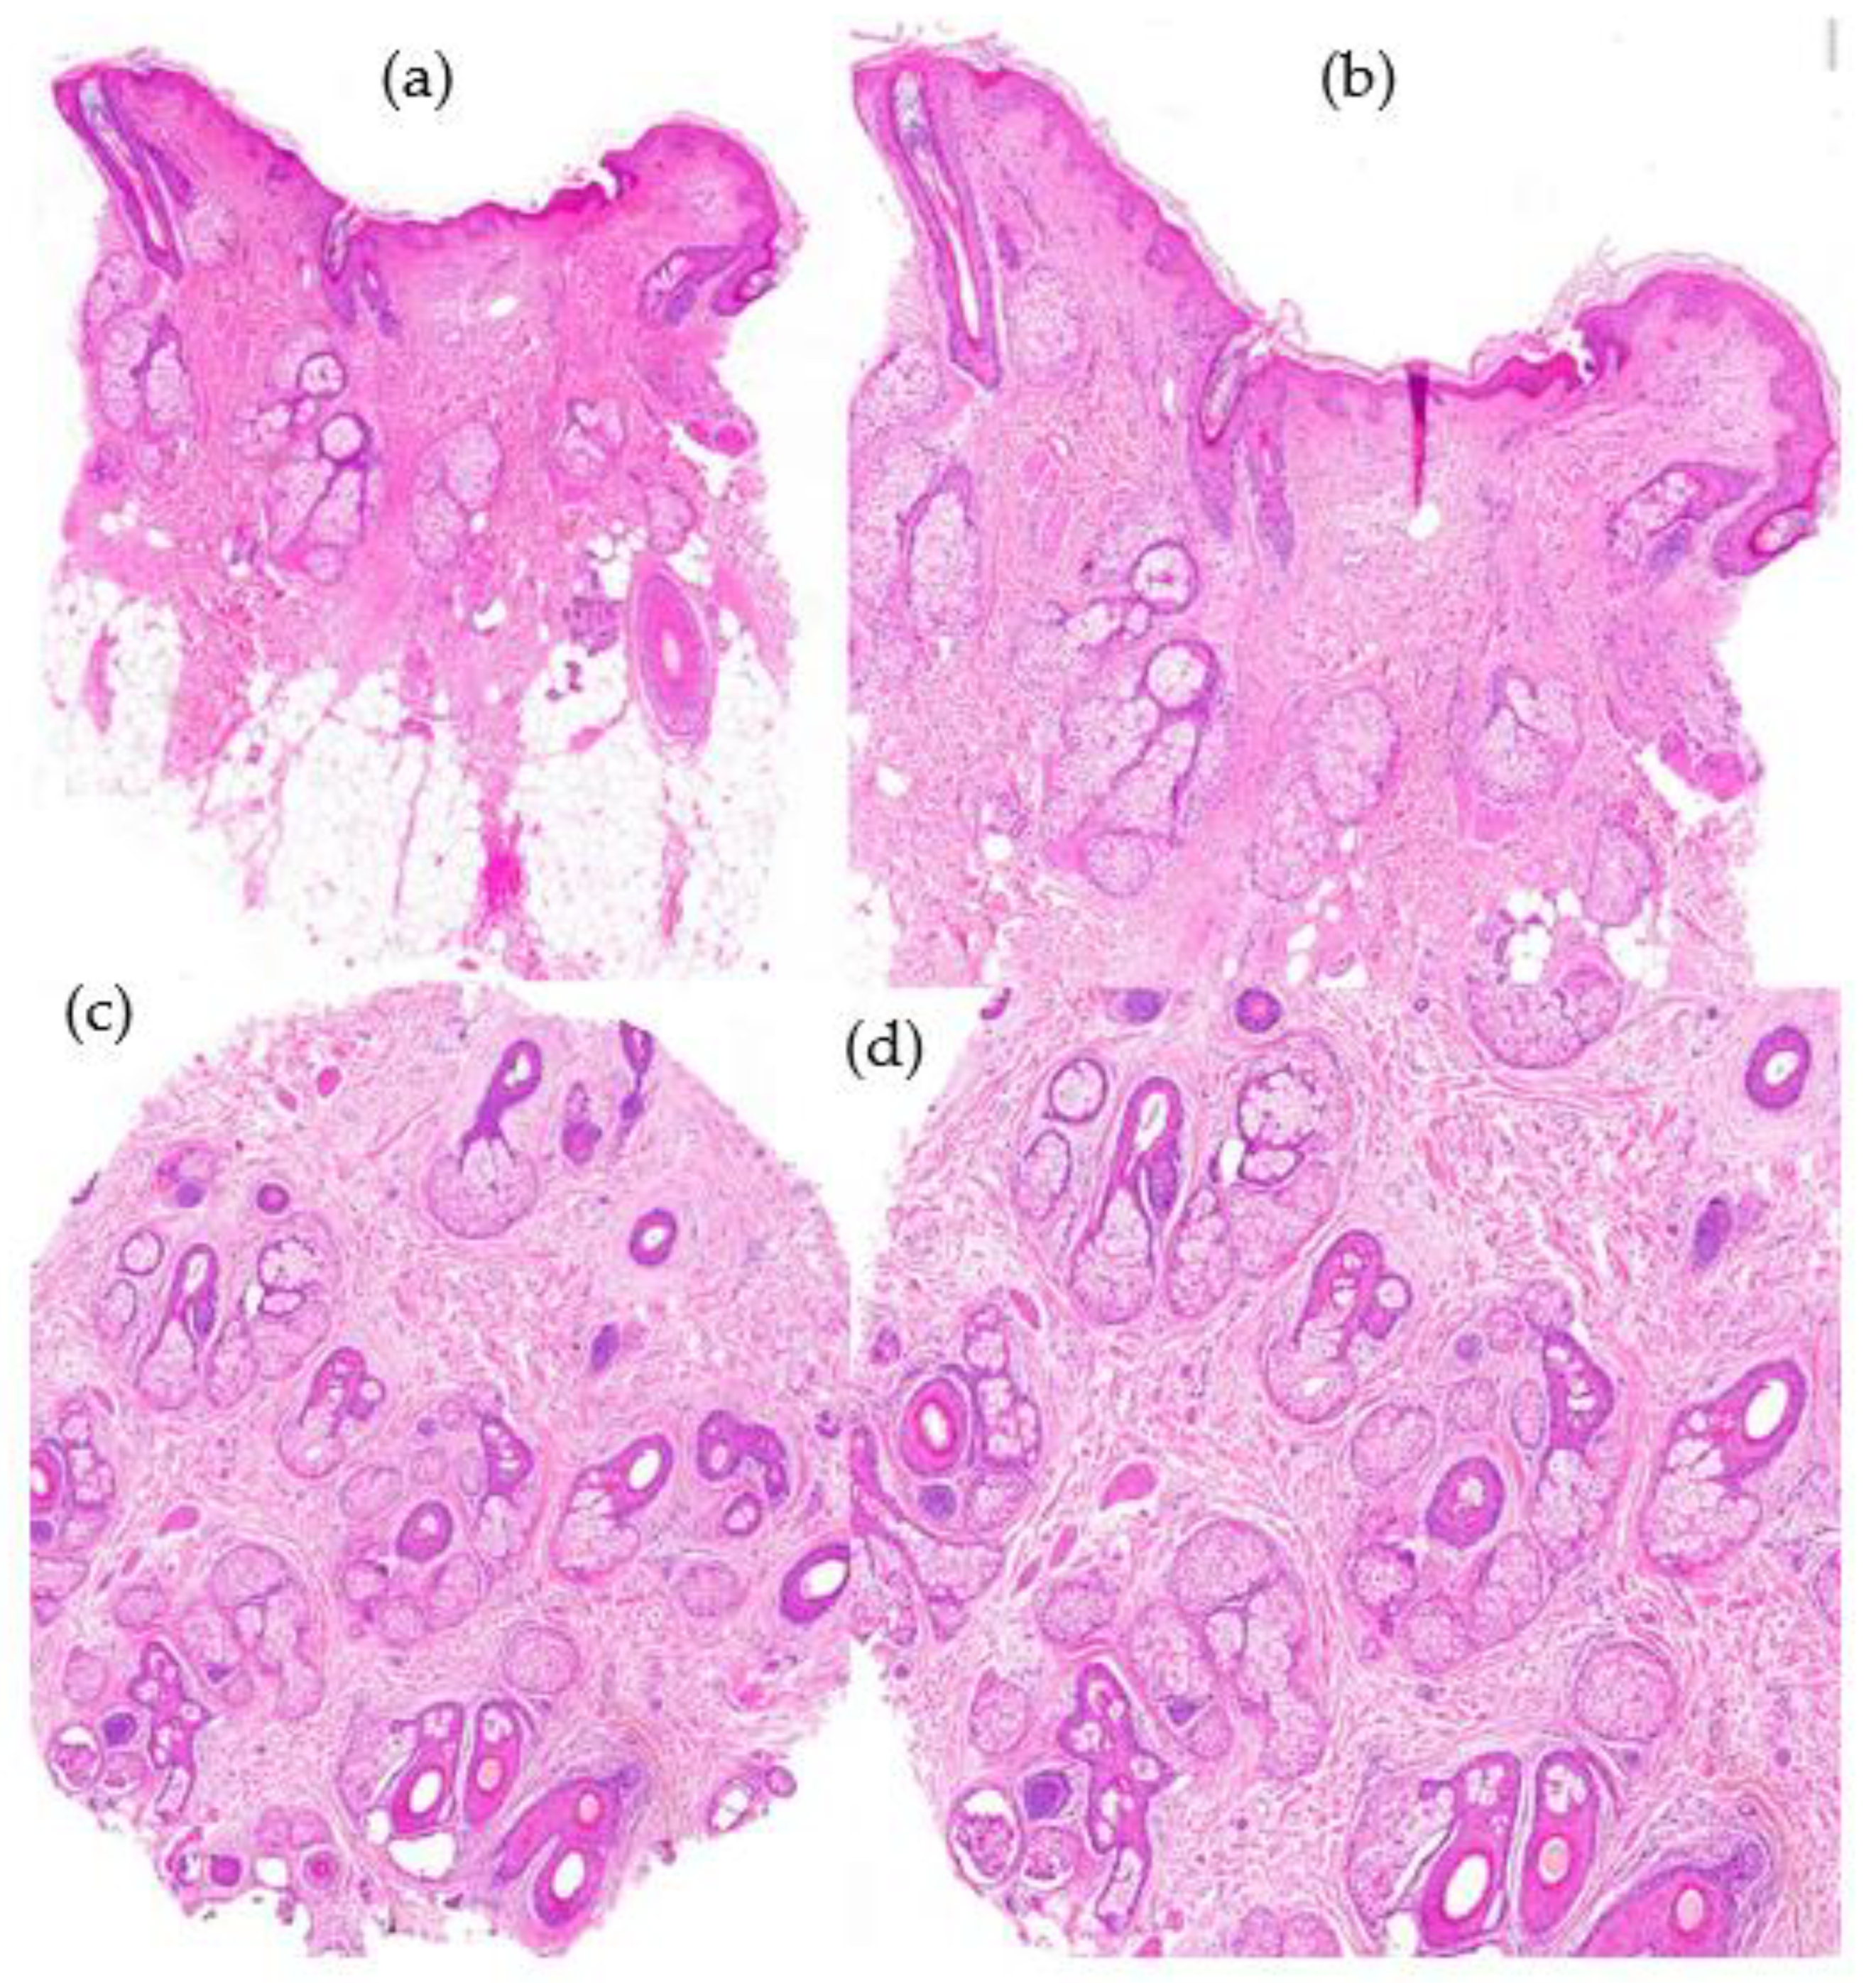

- Histological Features (Figure 7):

- -

- Increase in the vellus index: miniaturization of terminal hair.

- Increase in the telogen index.

- Sebaceous gland pseudohyperplasia.

- Perifollicular lymphocytic infiltrate (70%).

- Absence of concentric fibrosis.

- Polarized light: negative birrefringence of follicular streamers/stelae.